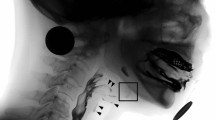

For labeling the points of interest on VFSS image, engineers of AetherAI Co., Ltd. constructed a web-based labeling interface software with the front-end framework built up with the Angular platform (Ver. 10.1.4) and the backend framework built up with Django framework (Ver. 2.2.10). With this web-based labeling software, users could not only mark the points of interest but also adjust the contrast of each image frame in order to improve the accuracy during image labeling. Two trained physiatrists (K.-C.W. and S.-H.C.) and two speech and language pathologists (Y.-C.W. and Y.-Y.P.) marked the following points of interest in each video frame using the AetherAI platform (Fig. 1): (1) anterior–inferior corner of the C2 vertebral body, (2) anterior–inferior corner of the C3 vertebral body, (3) anterior–inferior corner of the C4 vertebral body, (4) anterior–inferior corner of the C5 vertebral body, (5) anterior–inferior corner of the hyoid bone, and (6) the most prominent point at anterior–inferior corner of the mandible bone. To further conduct the hyoid kinematic analysis, a coordinate axis was defined with the anterior–inferior corner of the C4 vertebral body set as the origin. The y-axis was defined as the line connecting (2) and (4). The perpendicular line intersecting with (3) was defined as the x-axis. Based on the established coordinate axis, the anterior-inferior corner of the hyoid bone then possessed a position coordinate and parameters including the maximal displacement of hyoid bone during swallowing, the maximal displacement in the x-axis direction, and the maximal displacement in the y-axis direction were recorded. The maximal displacement of hyoid bone was the hypotenuse displacement from the origin calculated with Pythagorean theorem. The distance was measured by transforming the image pixels to corresponding millimeters (mm) and time duration between start and end points of hyoid movement in one swallow was recorded. The starting point was defined as recognizable initiation of hyoid motion while the end point was defined as termination of hyoid motion after swallowing. The average velocity of the hyoid bone movement including the x-vector and y-vector components were also calculated by dividing the hyoid bone displacement by the duration of hyoid movement.